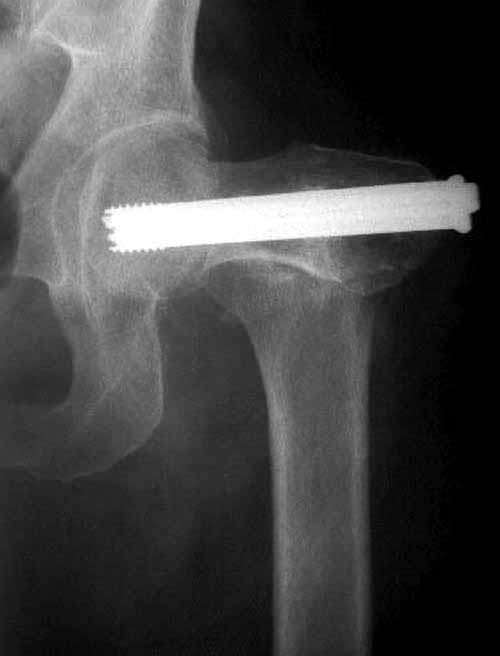

Как отметили коллеги, необходимо обратить внимание на последовательность введения каннюлированных шурупов. Рекомендуется введение в форме “V”, т.е основанием вниз, потому что в другой последовательности за счет увеличения стресса латерального кортекса имеется риск перелома. За редким исключением удается установить Guide wire с первой попытки и многоразовые пробы спицей увеличивают стресс. Небольшая травма может привести к перелому.

Работа Burstein AH and Wright TM: Fundamentals of Orthopaedic Biomechanics. Williams & Wilkins, Baltimore, pp. 160-169, 1994 доказывает, что шурупы, введенные на уровне малого вертела или ниже, приводят к осложнению. Введенные шурупы под 135 и больше градусов в 20% осложнились подвертельными переломами бедра.